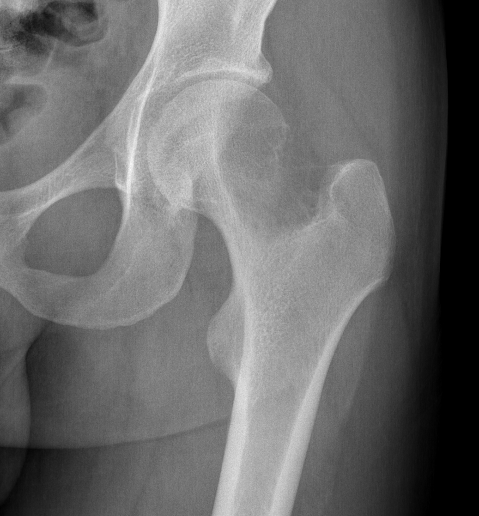

X-ray

Eccentric, sharply demarcated lytic lesion

- no sclerosis around lesion

- narrow zone of transition

- metaphysis, extending into epiphysis

- no mineralization

Wide resection and Allograft / Prosthesis Reconstruction

Indications

- extensive soft tissue tumour

- extensive cortical destruction

- impossible joint salvage

- multiple recurrence / failure bone cement

Distal Radius